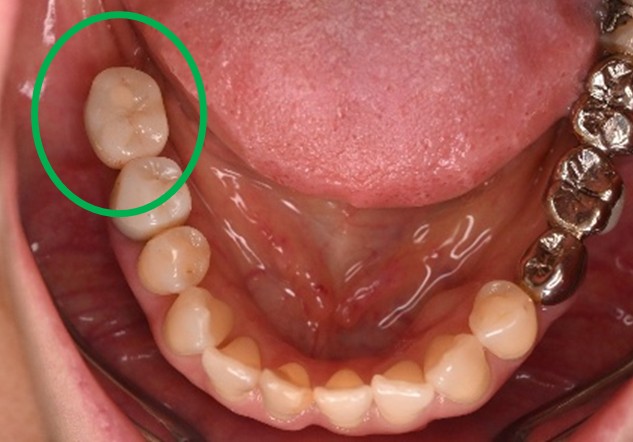

男性 Eさん 80代 (インプラント)

主訴

左上2本が動いていて、噛むと痛みがある。歯がないところに歯を入れたい。

治療内容

左上第二小臼歯と第一大臼歯の歯根が破折していたため、保存することができず抜歯しました。第一小臼歯は、すでにありませんでしたので、2本抜歯後3本欠損のところにインプラントを2本埋入しました。

所感

2006年10月に右下と左下の欠損部分にインプラント治療をしました。今回も左上の歯を失ったところは、インプラント治療を希望されました。

インプラント2本:¥363,000✕2本=¥726,000(税込)

ポンティック1本:¥115,500(税込)

合計:¥841,500(税込)

Before

※赤丸は、歯根が破折していたため抜歯しました

※黄色丸は、2006年10月に埋入したインプラント

After

※緑丸は、今回埋入したインプラント